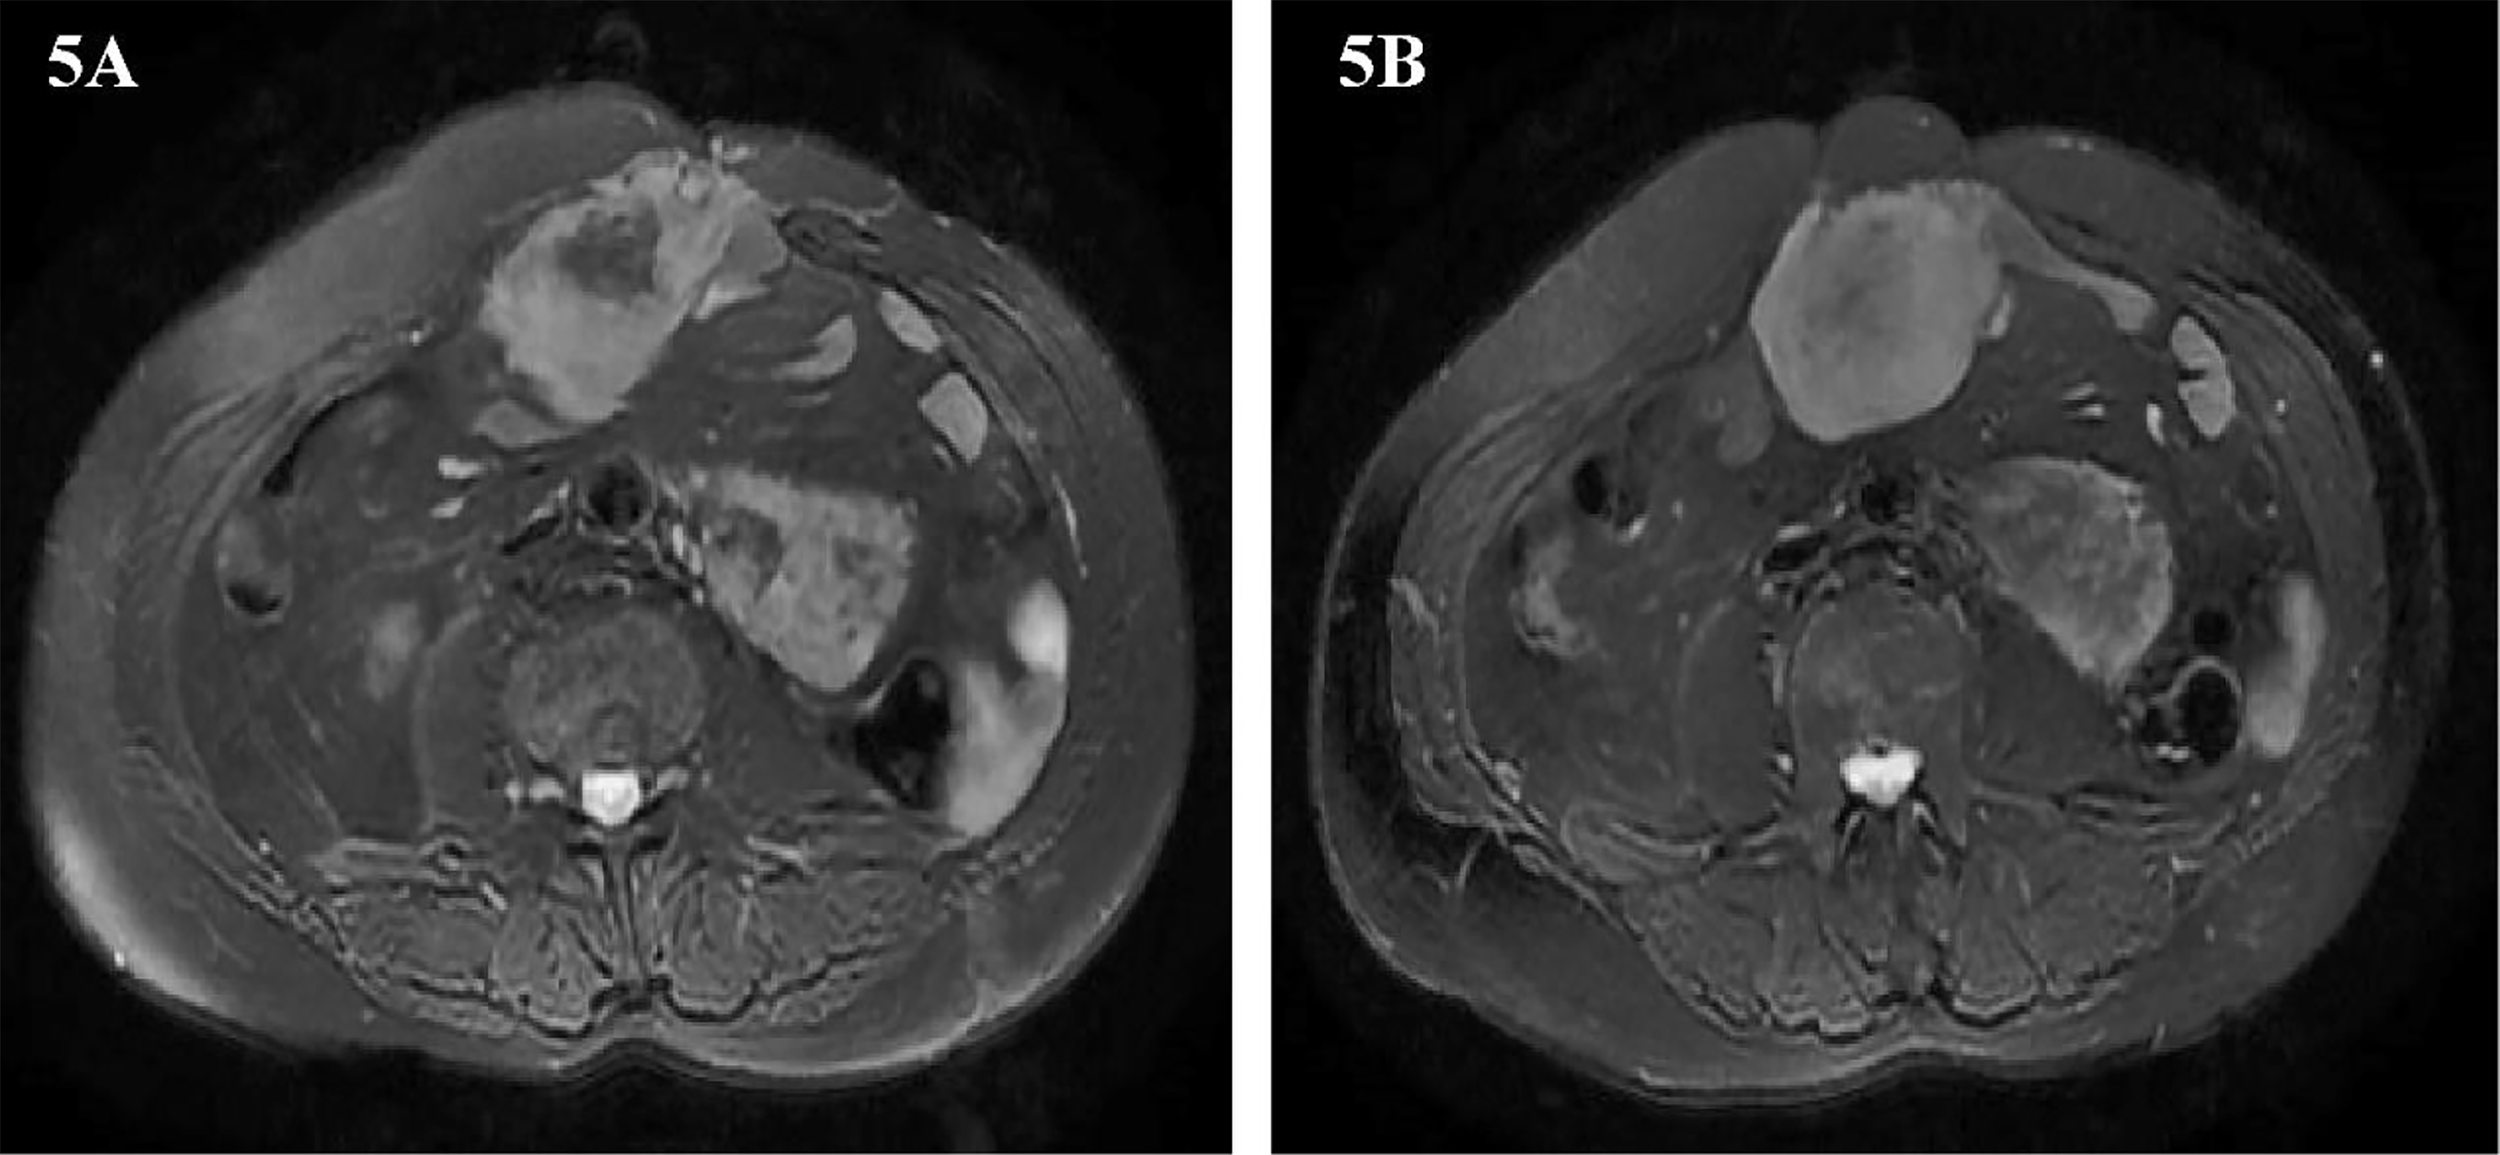

Two years later, abdominal MRI showed abnormal signal shadow on the lower edge of the spleen again, and metastasis was considered. There were tumors around the operation area and the inner edge of the anterior abdominal wall incision. Multiple space-occupying lesions in the abdominal cavity, considering the possibility of malignant tumor recurrence and metastasis (Figures 5A, B). The multidisciplinary team of experts (MDT) assessed the patient’s condition and believed that the operation could be performed. Our team performed the fifth operation on the patient on December 8, 2016. Operation name: Retroperitoneal tumor resection + partial splenectomy + partial small bowel resection + intestinal adhesion lysis + abdominal wall tumor resection. The sarcoma encapsulates the distal end of the spleen and occupies a small area. Considering the low risk of the spleen at the margin of resection, it was decided to remove the sarcoma along with part of the spleen. This partial splenectomy is not related to the previous partial splenectomy. The spleen part of the two excisions was small, which did not affect the function of the spleen, and there was no postoperative bleeding. The postoperative pathology was dedifferentiated liposarcoma, some areas showed rhabdomyosarcoma differentiation, and some areas showed malignant fibrous histiocytoma. Immunohistochemistry: Pathological section No. 3: SMA(+), S100(+), CD68(+), MyoD1(-), Myogenin(-), HMB45(-), Ki-67 positive rate is about 20%. Pathological section No. 3: SMA(+), MyoD1(+), Myogenin(+), CD68(-), HMB45(-), S100(-), Ki-67 positive rate is about 20%. The patient was discharged on the 11th day after surgery.

Figure 5

(A, B) Abdominal image before the fifth operation.